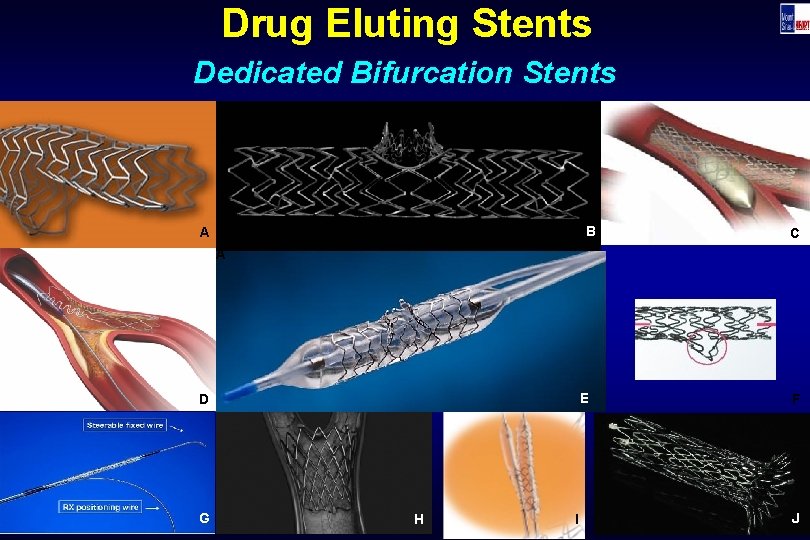

Drug Eluting Stents Dedicated Bifurcation Stents B A C A E D G H I F J